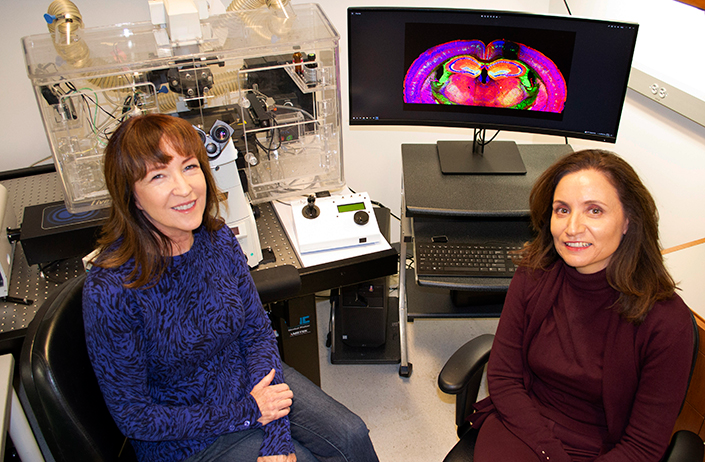

Professor Shelley Halpain (left) and Associate Project Scientist Barbara Calabrese.

Professor Shelley Halpain (left) and Associate Project Scientist Barbara Calabrese.